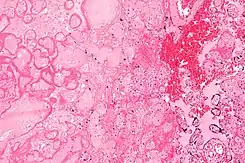

![]() Microfotografía de un infarto de la placenta (a la izquierda de la imagen), una causa de la hipoxia intrauterina. Tinción de H&E. | ||